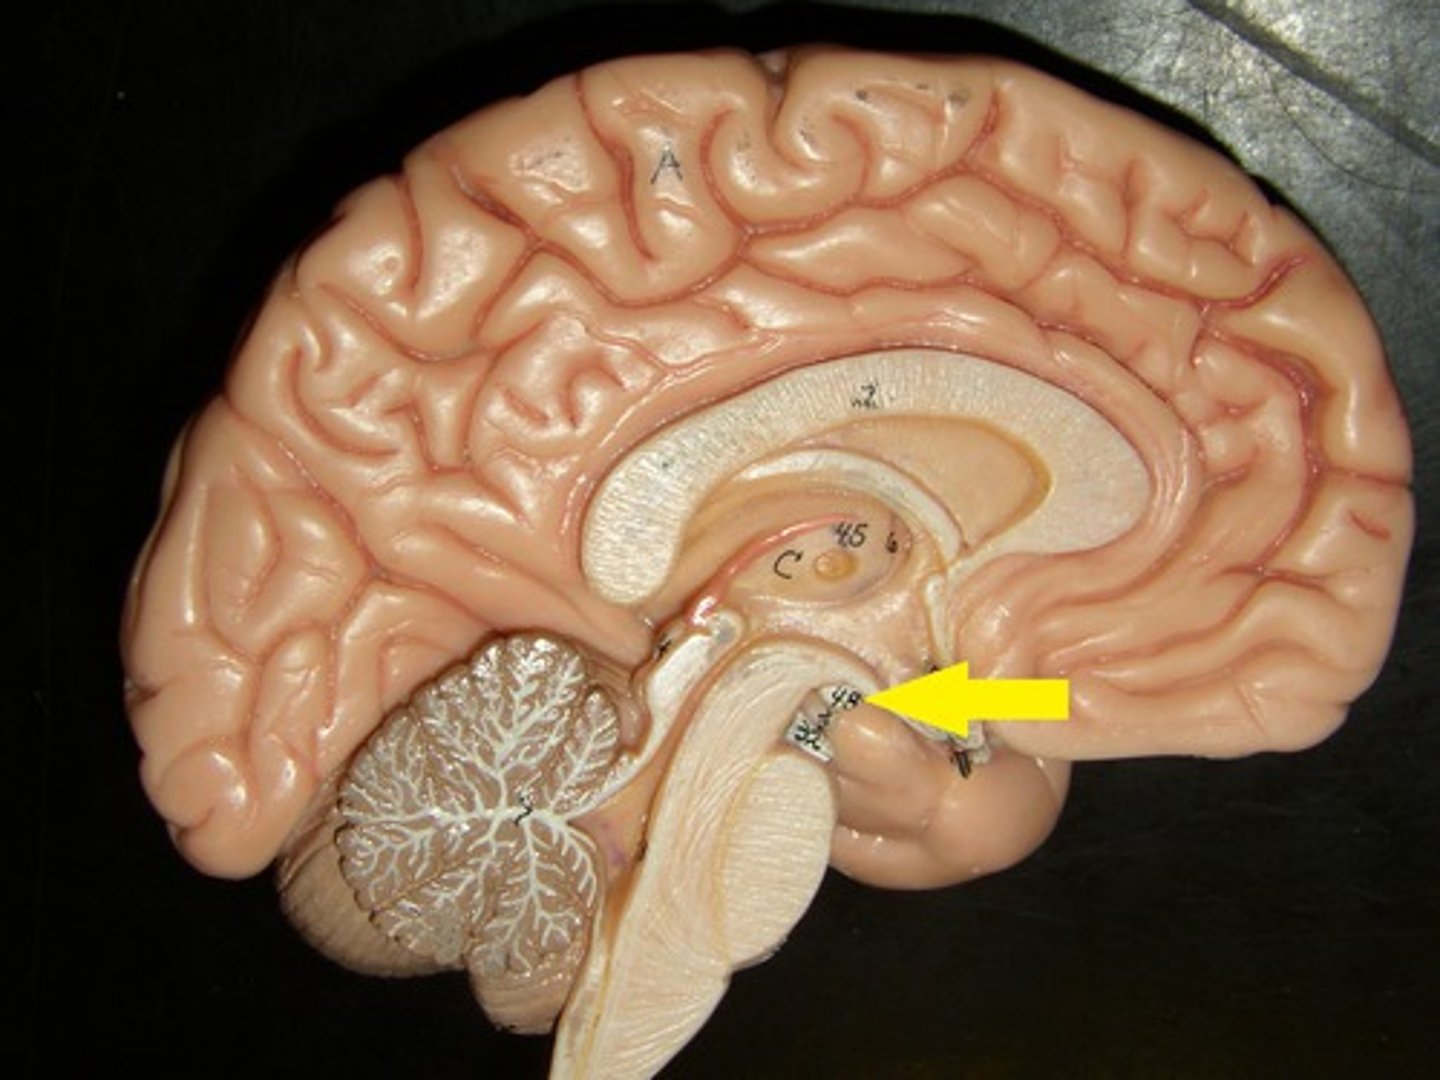

Circulation of CSF

CSF from the lateral ventricles → interventricular foramina → third ventricle → cerebral aqueduct → fourth ventricle → subarachnoid space or central canal.